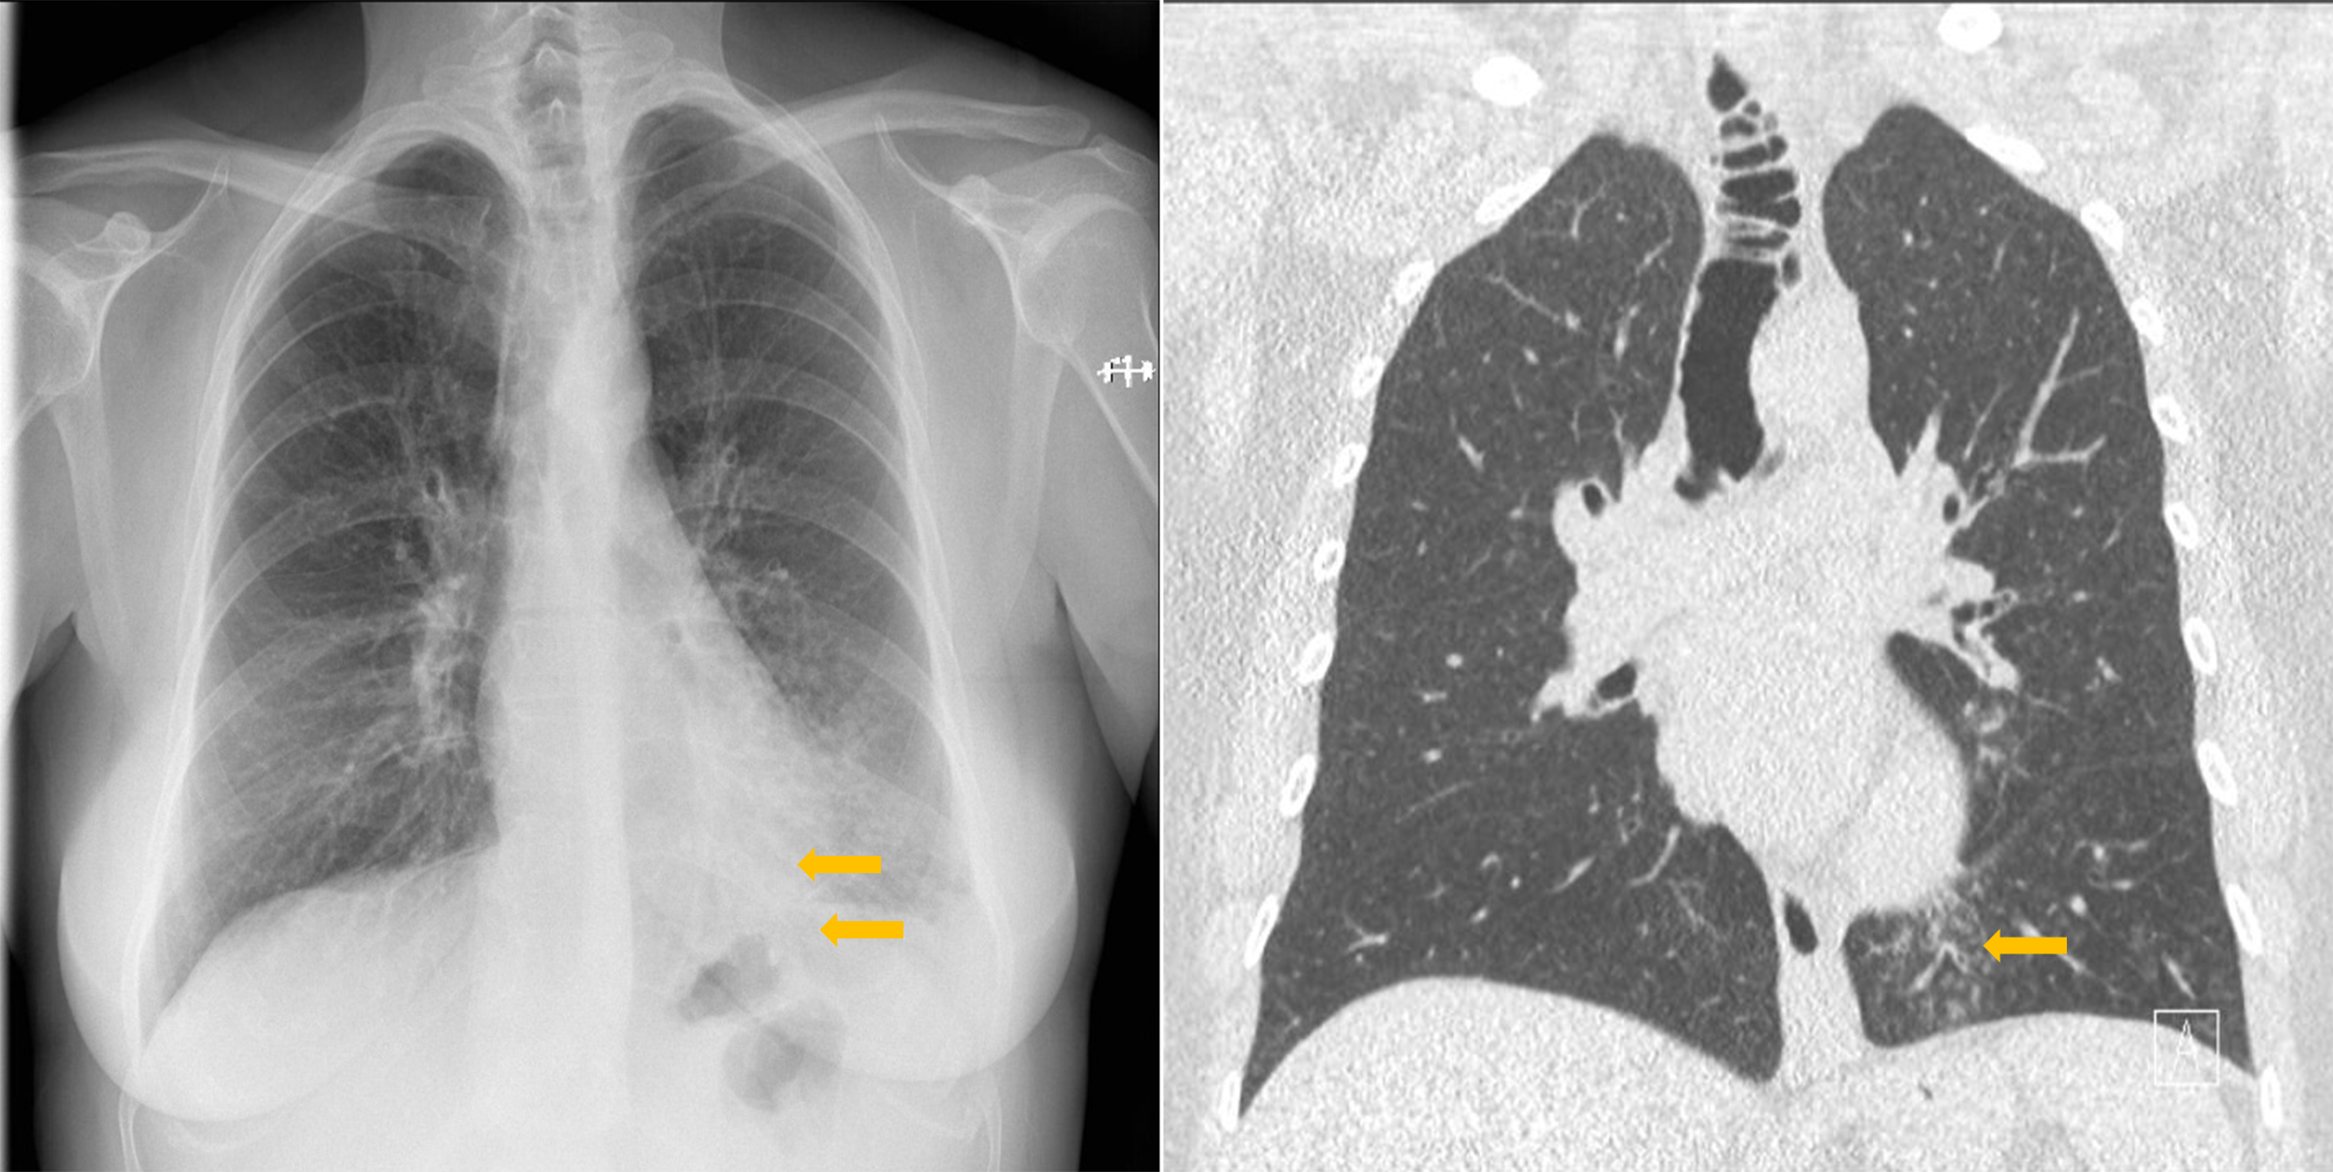

Figure 1

Tracheal diverticulosis and left bronchiolitis; frontal CXR and CT comparison.